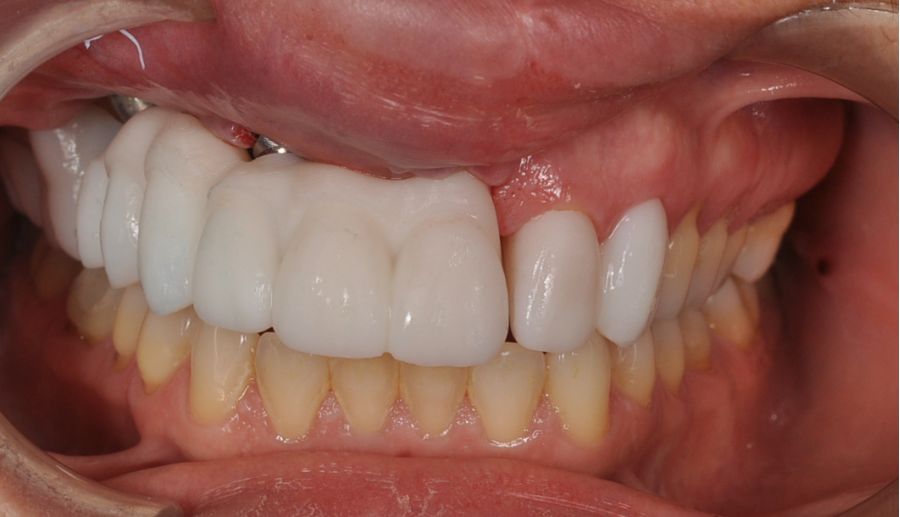

Una vez finalizada la radioterapia, la paciente se encontraba libre de enfermedad. Por lo que se procedió a la restauración definitiva implantosoportada. Tras la segunda fase, se colocaron dos pilares transepiteliales Multiunit Ò rectos y un pilar Multunit Ò angulado de 17º (Figura 10).

Para la fabricación de las estructuras, se eligió el óxido de zirconio monolítico como material restaurador sobre interfases metálicas en el puente implantosoportado, y coronas de óxido de zirconio monolítico en los dientes tallados previamente (1.7, 1.6, 2.2 y 2.3). Se tomaron impresiones de cubeta abierta con silicona de adición pesada y fluida (Zhermack Elite HD, Gmbh). Se realizó una prueba de pasividad analógica y el resto del proceso se confeccionó de manera digital, por lo que se hicieron pruebas estéticas de dientes impresas en 3D sobre interfases metálicas, para hacer todos los ajustes de función y estética previos al fresado del zirconio monolítico (Figuras 11, 12 y 13).

El día de la colocación de las estructuras, se arenó el interior de las coronas dentosoportadas con óxido de aluminio de 50 m y fueron cementadas con cemento de resina Multilink Ò. El puente implantosoportado se atornilló al torque indicado (20Nw) (Figuras 14, 15, 16 y 17).

En enero de 2021, el puente implantosoportado fue atornillado con un torque controlado (20 Nw), y las coronas dentosoportadas cementadas con éxito. La paciente refirió una notable mejoría en la función masticatoria, fonación y estética facial, manifestando un alto grado de satisfacción.